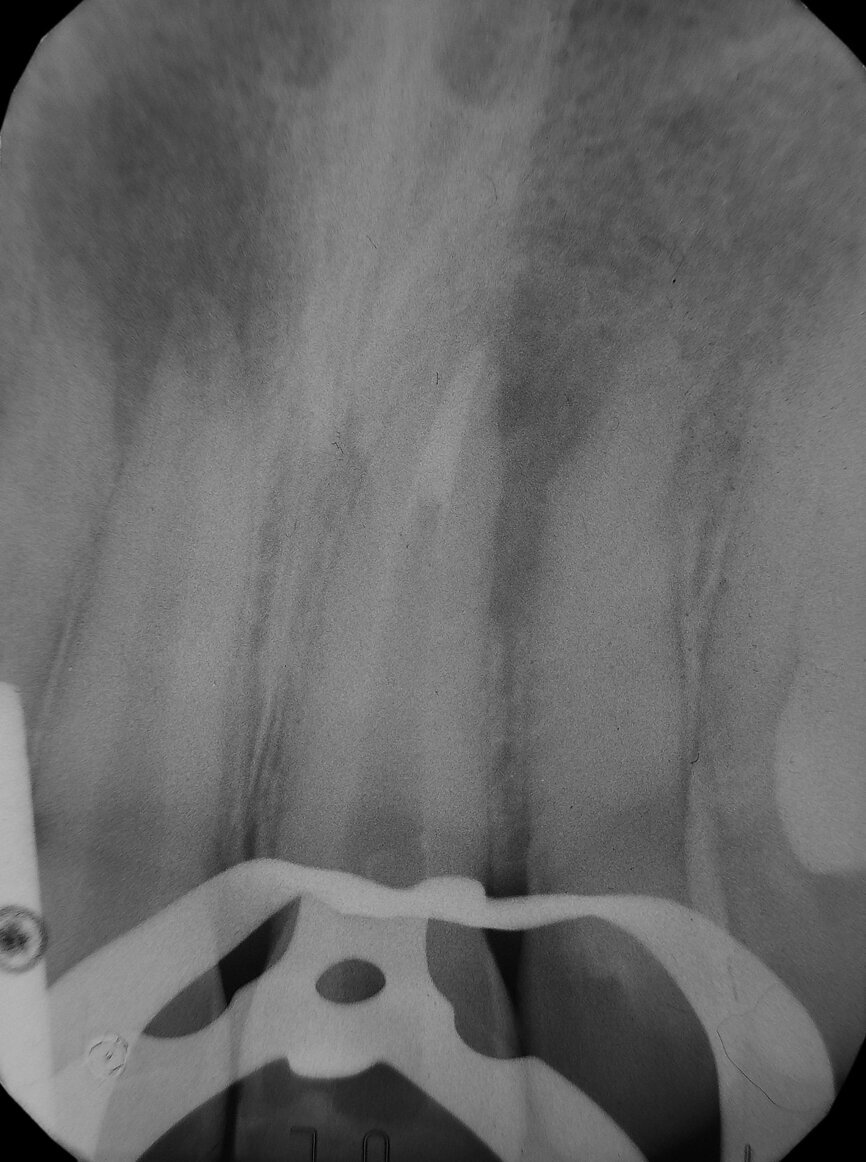

The symptoms resolved, so I conducted the second treatment only after some months, when the tooth #11 became tender. Tooth #21 had healed. I performed the same procedure and obtained the same outcome (the four-month follow-up radiograph showed healing).